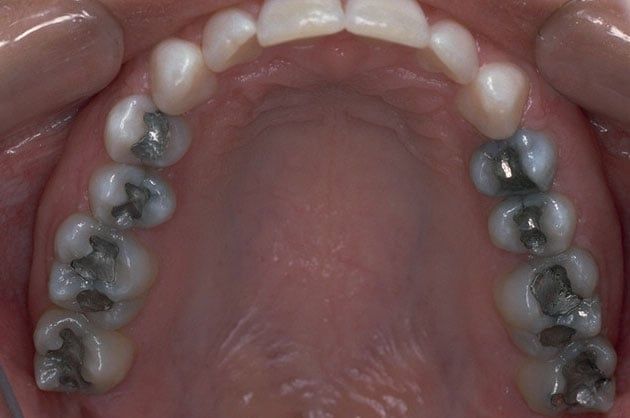

Replacing Old Silver Or Gold Amalgam Fillings

John W. Schulz, D.D.S. specializes in beautiful cosmetic dentistry. Metal fillings are often thought of as an eyesore especially with the front teeth that are visible to everyone when you smile. We are able to remove those old metal fillings and replace them with today's white fillings which are nearly identical in color to the teeth that they are in.

Virtually everyone is a candidate to have metal fillings replaced with natural-looking white fillings. Request an appointment online or call our office directly at 415.731.9300 to discuss replacing your old metal fillings with white ones.